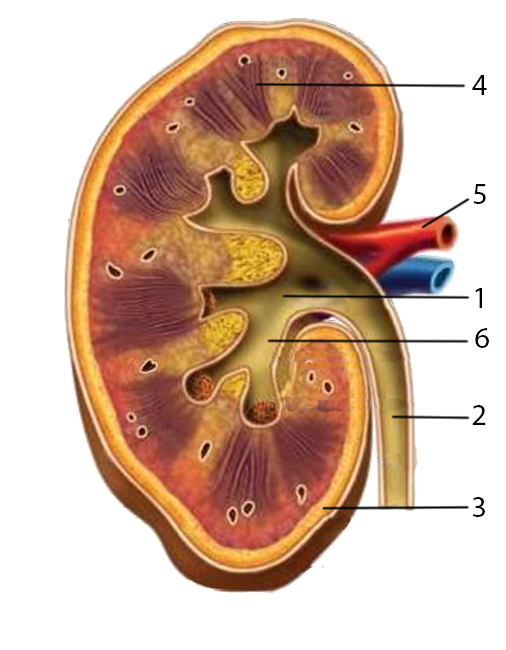

Интраренальная лоханка: рентгеновские снимки и примеры